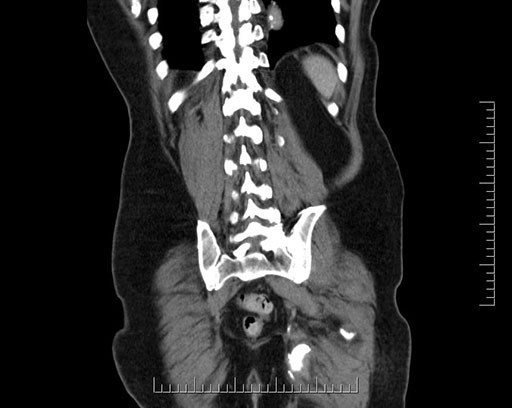

Whipple (pancreaticoduodenectomy) [case 7]

Imaging Analysis

Look through the patient's CT scan to identify any areas of concern for the necessary procedure.

Based on your CT findings, which issue(s) would give reason for "planned slowing down moment(s)" in this case?

Considering a standard Whipple procedure, what step(s) of the operation would you do differently in this case?